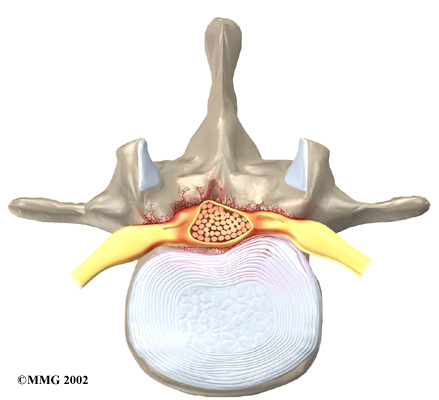

Disc herniation: Spinal stenosis can occur when an intervertebral disc in the low back herniates (ruptures). Normally, the shock-absorbing disc is able to handle the downward pressure of gravity and the strain from daily activities. However, if the pressure on the disc is too strong, such as landing from a fall in a sitting position, the nucleus inside the disc may rupture through the outer annulus and squeeze out of the disc. This is called a disc herniation. If an intervertebral disc herniates straight backward, it can press against the nerves in the spinal canal, causing symptoms of spinal stenosis.

Disc Herniation

The lamina is the covering layer of the bony ring of the spinal column. It forms a roof-like structure over the back of the spinal canal. When the nerves in the spinal canal are being squeezed by a herniated disc or bone spurs, a lumbar laminectomy removes the entire lamina to release pressure on the spinal nerves. This is the primary type of surgery used for lumbar spinal stenosis.